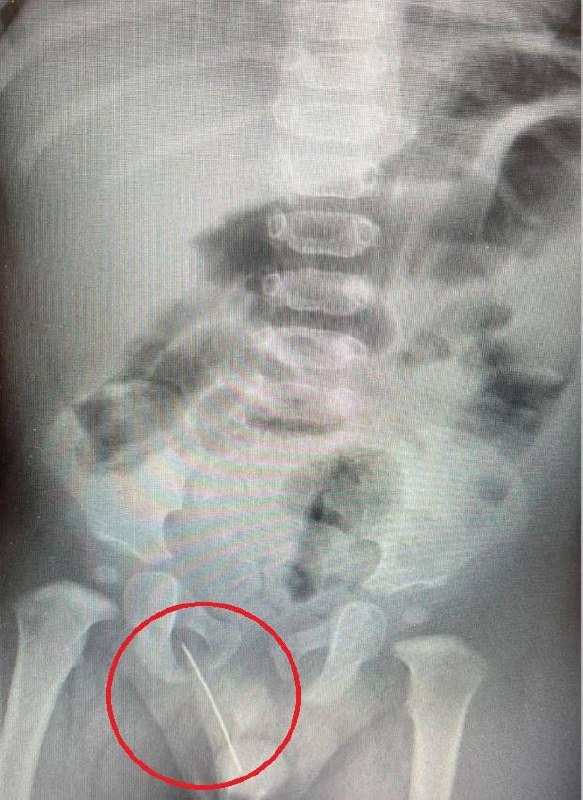

👩‍⚕️ В Подмосковье спасли годовалого ребенка, который сел на иголку. Острие вошло в мягкие ткани и угрожало внутренним органам, из-за резкой боли мальчик даже не мог встать на ноги. На скорой ребенка привезли в Детский научно-клинический центр имени Л.М. Рошаля. Рентген показал металлическое инородное тело в малыше: «Инородным телом стала швейная игла, которая прошла в опасной близости от уретры. Вероятнее всего, мальчик случайно сел на нее. Мы выполнили ребенку экстренную операцию по извлечению инородного тела, после которой болевой синдром был полностью купирован. Операция прошла успешно, без осложнений», — сказал заведующий отделением детской хирургии №1 Евгений Рожденкин. Москва. Новости 24/7